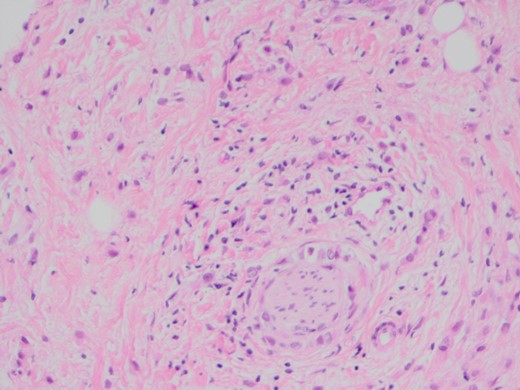

When she now presented with generalized abdominal pain, a CT scan of the abdomen was performed, revealing a lesion in the head of the pancreas measuring 7 × 4 cm2. This mass extended into the porta hepatis and towards the left lobe of the liver, opacification of the splenic vein and superior mesenteric veins was absent, and the confluence of the portal vein could also not be visualized (Fig. 1). Total bilirubin was 13 μmol/L (normal <20), raised ALT at 127 U/L (normal <34) and AST at 69 U/L (normal <31). ALP and GGT were also mildly raised at 135 U/L for ALP (normal 30–110) and 219 U/L for GGT (normal <38). Carcinoembryonic antigen and CA19.9, both markers of pancreatic cancer, were not raised. She was referred to a hepatobiliary surgeon for consideration of a pancreaticoduodenectomy, with the assumption of a primary pancreatic lesion. Due to suspected vascular involvement and potential peritoneal disease seen on the CT, she was regarded as an unsuitable candidate for a pancreaticoduodenectomy. To consider the use of palliative chemotherapy, a percutaneous biopsy for tissue diagnosis was performed. Histology demonstrated a poorly differentiated tumour, surrounded by benign pancreatic tissue with focal areas of perineural invasion by GATA3 positive epithelial cells. These cells also stained positive for ER, K19 and CEA, but negative for PR, B72.3, E-cadherin and HER2. The final diagnosis was poorly differentiated lobular breast carcinoma. Unfortunately, we were unable to compare the expression profiles between the pathology from the axillary dissection and the metastatic disease (Figs 2–4).

The poorly differentiated carcinoma shows nuclear positivity for oestrogen receptor (IPX).